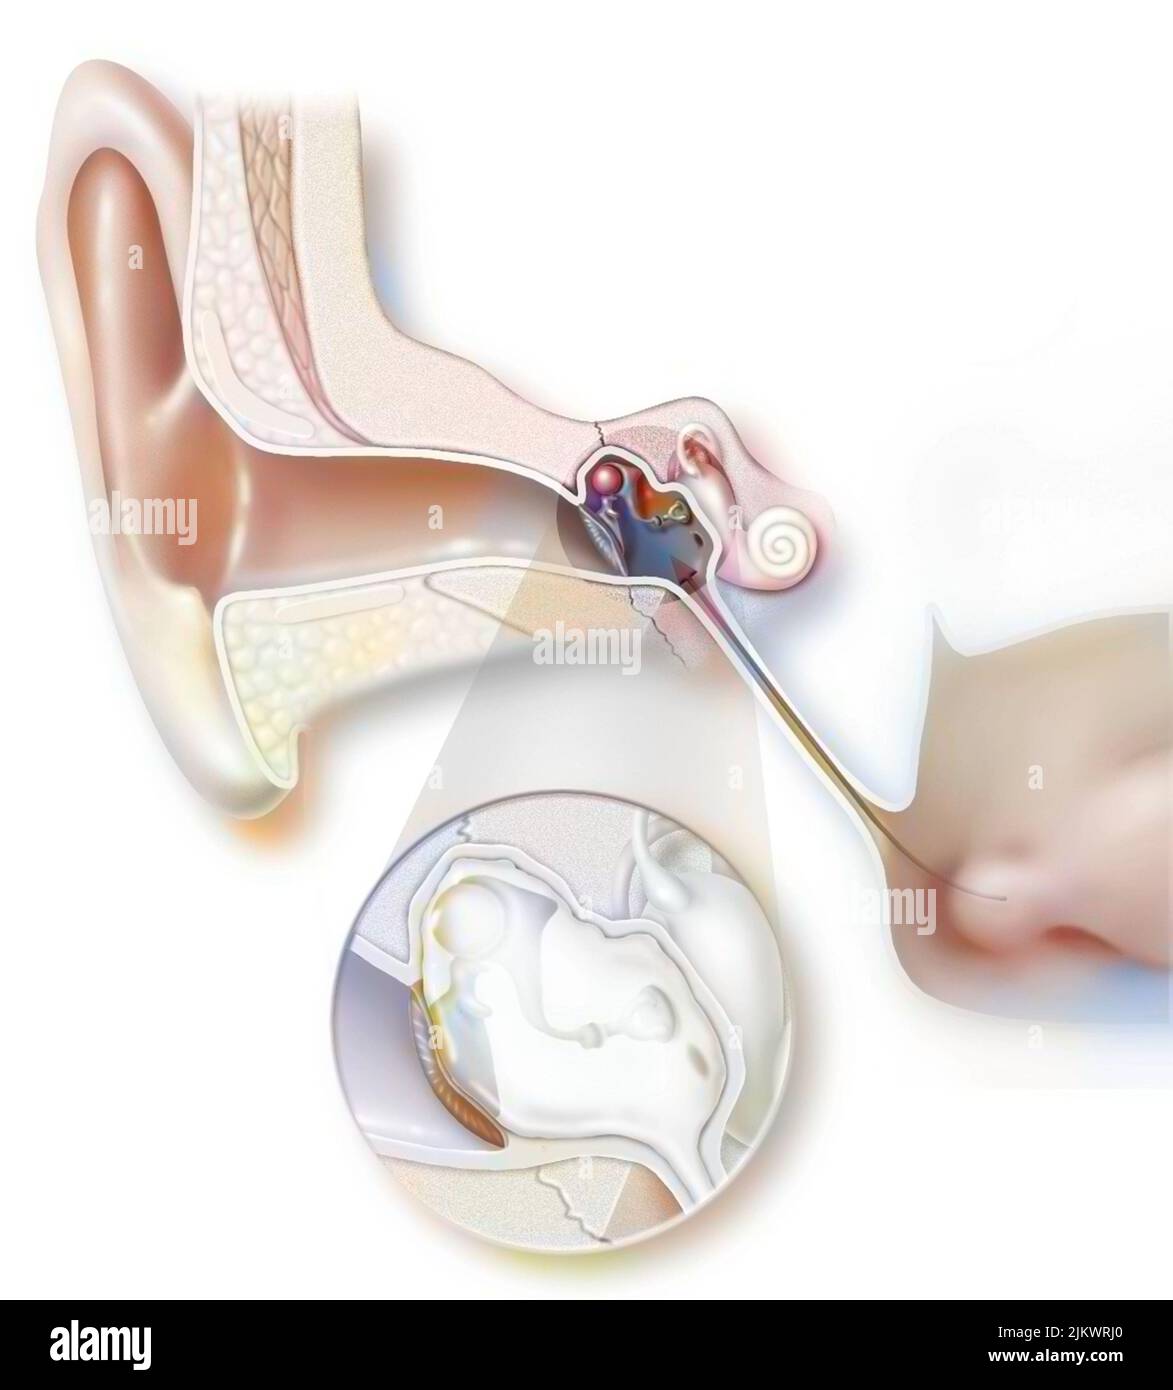

RF2JKWT9A–Oeil, cataracte, phacoémulsification - étape 2: Consiste à casser la lentille avec une sonde.